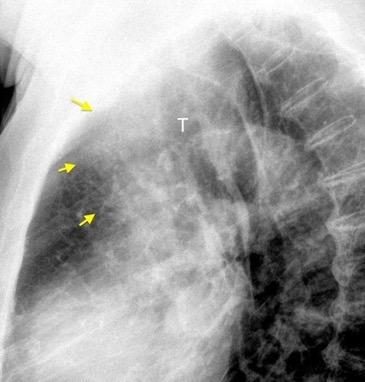

Raro. (2-9% de los T. tímicos). Asintomático. Contiene grasa (hasta 90%) y tejido timico (10-33%). Pueden ser muy grandes y confundirse con cardiomegalia. La tomografía “clásica” muestra los límites de la silueta cardiaca. (flechas)